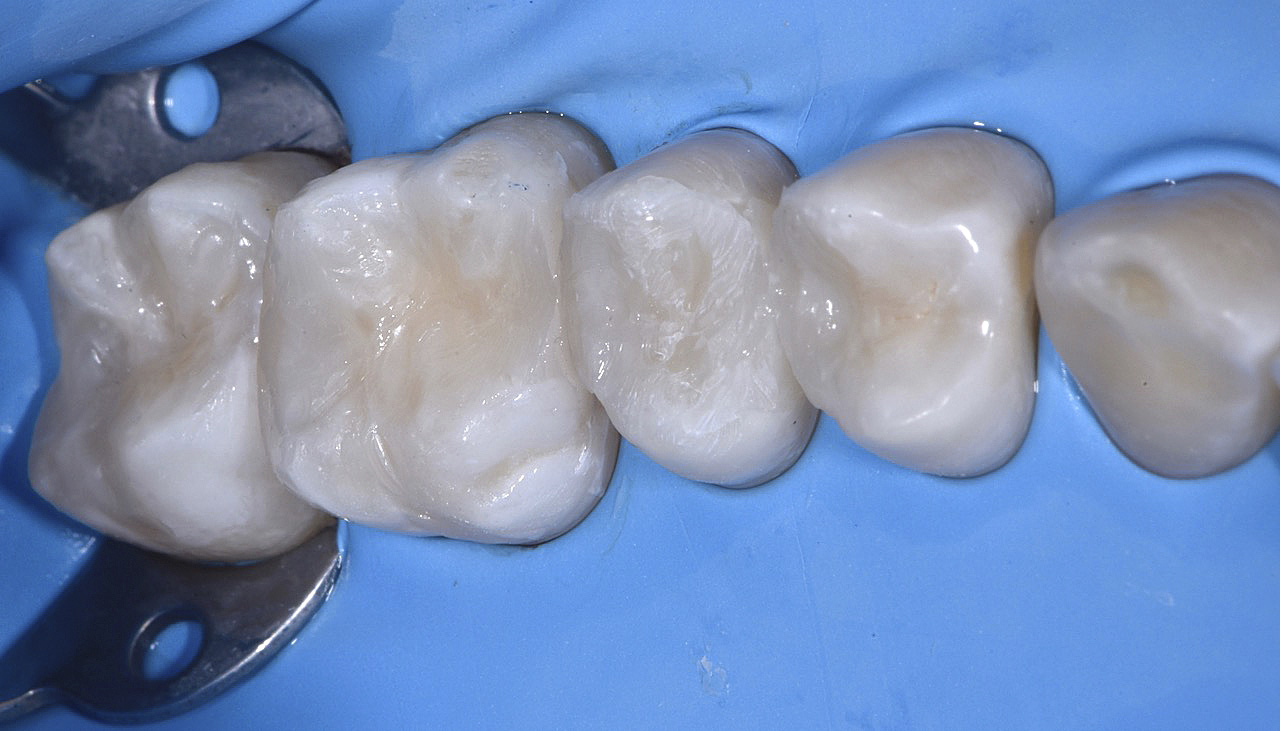

Vengono utilizzati 2 tipi di provvisori: il primo, cementato ai denti vicini, viene utilizzato dal momento dell’estrazione del dente fino ad impianto osteointegrato (circa 6 mesi); il secondo, avvitato direttamente all’impianto, ha una funzione di prova estetica ma soprattutto di guida per la maturazione dei tessuti gengivali peri-implantari portandoli verso la maturazione completa prima di posizionare la corona finale in disilicato di litio.